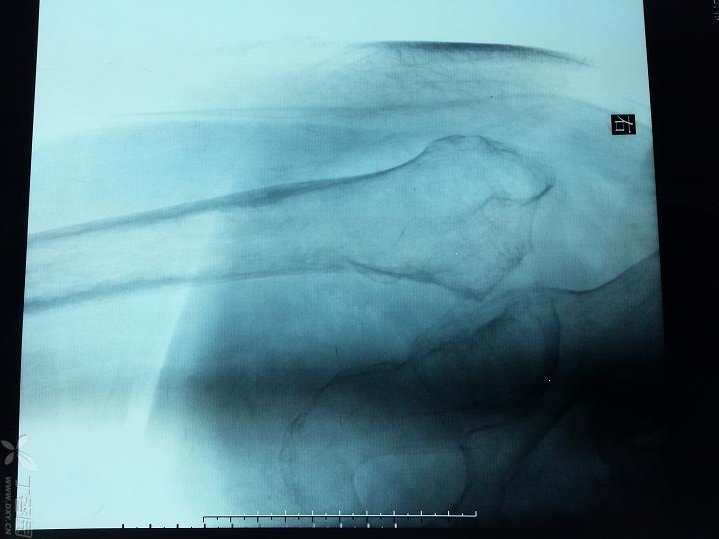

查体:心肺腹未见明显异常,右下肢短缩3厘米,右髋关节活动受限,右下肢无明显水肿,无明显感觉异常,膝上10厘米右侧大腿周径较左侧减少约2厘米,右小腿周径较左侧减少约1厘米,末梢血运好好。X片如下,右股骨颈陈旧性骨质,髋臼侧及股骨侧继发骨质疏松。CT检查显示右股骨颈骨质,股骨近端骨质未见明显破坏。

CT测得股骨头直径约46mm,股骨小转子下10厘米髓腔左右径约17-18mm,